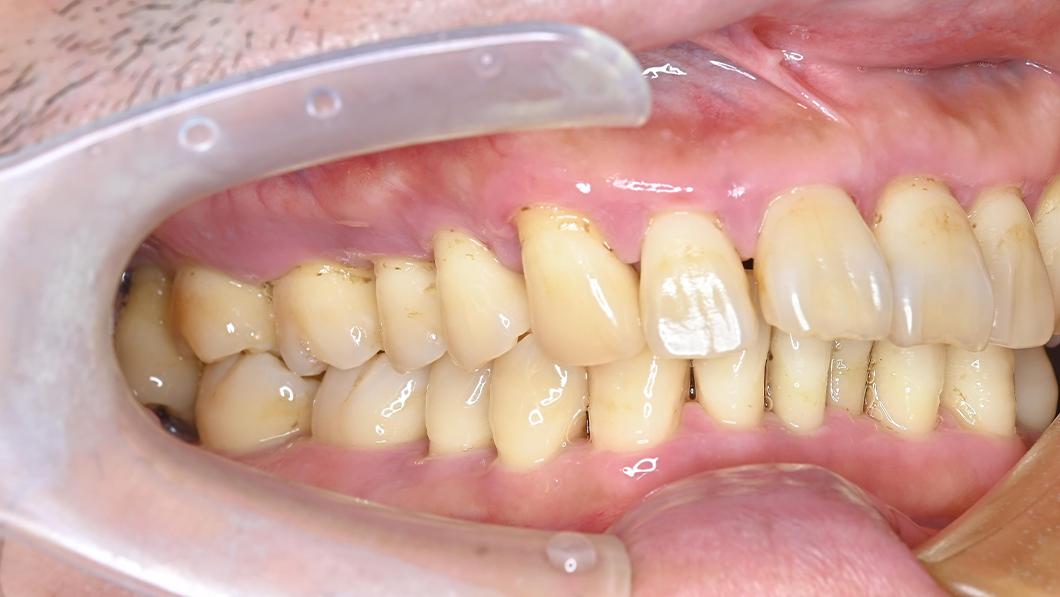

【40代 男性】歯周基本治療

治療前

主訴 全額的歯周病による歯周組織の炎症

治療内容 SC、SRP、歯科衛生士実地指導、TCH指導